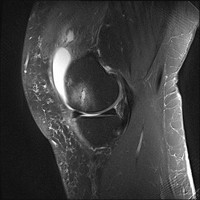

Schaden Hobbyläufer ihren Knien?

Immer mehr Menschen halten sich mit Joggen fit, und immer wieder taucht die Frage auf, ob sie damit ihren Knien schaden. Wissenschaftler versuchten durch die…

Kniearthrose: Gelenkspaltverengung kann durch eine Kombination aus Glucosamin und Chondroitin verringert werden

Die tägliche Einnahme einer Mikronährstoff-Kombination aus Glucosamin und Chondroitin kann die Gelenkspaltverengung und den Schmerz von Personen mit…